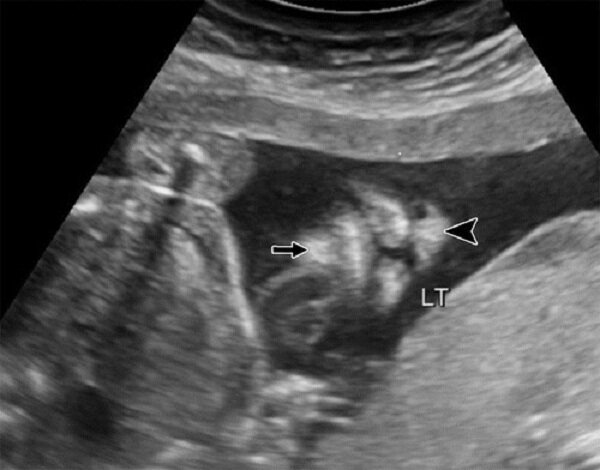

خبرگزاری مهر، گروه استانها - مرجان سیف الدین: شکاف لب به صورت پارگی یا فاصله در لب بالایی است که میتواند یک یا هر دو لب را درگیر کند و شدت آن از یک حفره کوچک تا بزرگ متغیر است. شکاف کام نیز سوراخ یا باز شدن در سقف دهان است که باعث جدا نشدن بافتهای دهان و بینی میشود.

معمارزاده توضیح داد: جنین از هفته چهارم شروع به تکمیل شدن میکند و لب بالا در هفته دوازدهم بارداری شکل میگیرد. بنابراین هر عاملی که در این دوران رخ دهد، میتواند منجر به نرسیدن لبهای جنین به یکدیگر شود و هر چه این عوامل زودتر اتفاق بیفتد، شدت شکاف لب و کام نیز بیشتر خواهد بود. وی بیان کرد: غربالگری در تشخیص این بیماری نقش موثری دارد، چرا که شکاف لب و کام به دلیل نقص در رشد بافتهای صورت در دوران جنینی ایجاد میشود و نیازمند عملهای جراحی اصلاحی پیشرفته است.